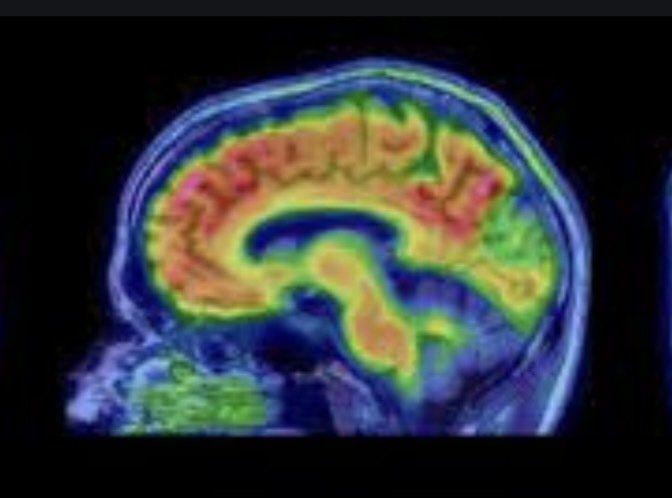

- Eine spezielle Bildgebung in Form eines PET-CT, bei dem auch der Glukosestoffwechsel im Gehirn dargestellt werden kann.

- Ist der Glucosestoffwechsel in Dystonie relevanten Hirnbereichen PET-CT-nachweislich zu hoch, steht eine hirnorganische Dystonieursache zur Rede.

Die für Dystonien neurologisch ursächlich zentralen Sende- bzw. Netzwerkstörungen - also fehlerhafte Prozesse auf Zellebene - lassen sich lediglich über ein sogenanntes PET-CT darstellen, einer Kombination aus Positronen-Emissions- und Computertomo-graphie. Nach Verabreichen eines radioaktiven Kontrastmittels, dass u.a. einen erhöhten Glukosestoffwechsel sichtbar machen kann, sind über dieses bildgebende Verfahren atypische energetische Prozesse, auch in der motorischen Schaltstelle unseres Gehirns, den Basalganglien, erkennbar, was wiederum eine Dystonie bzw. ihre Diagnose begründen kann.